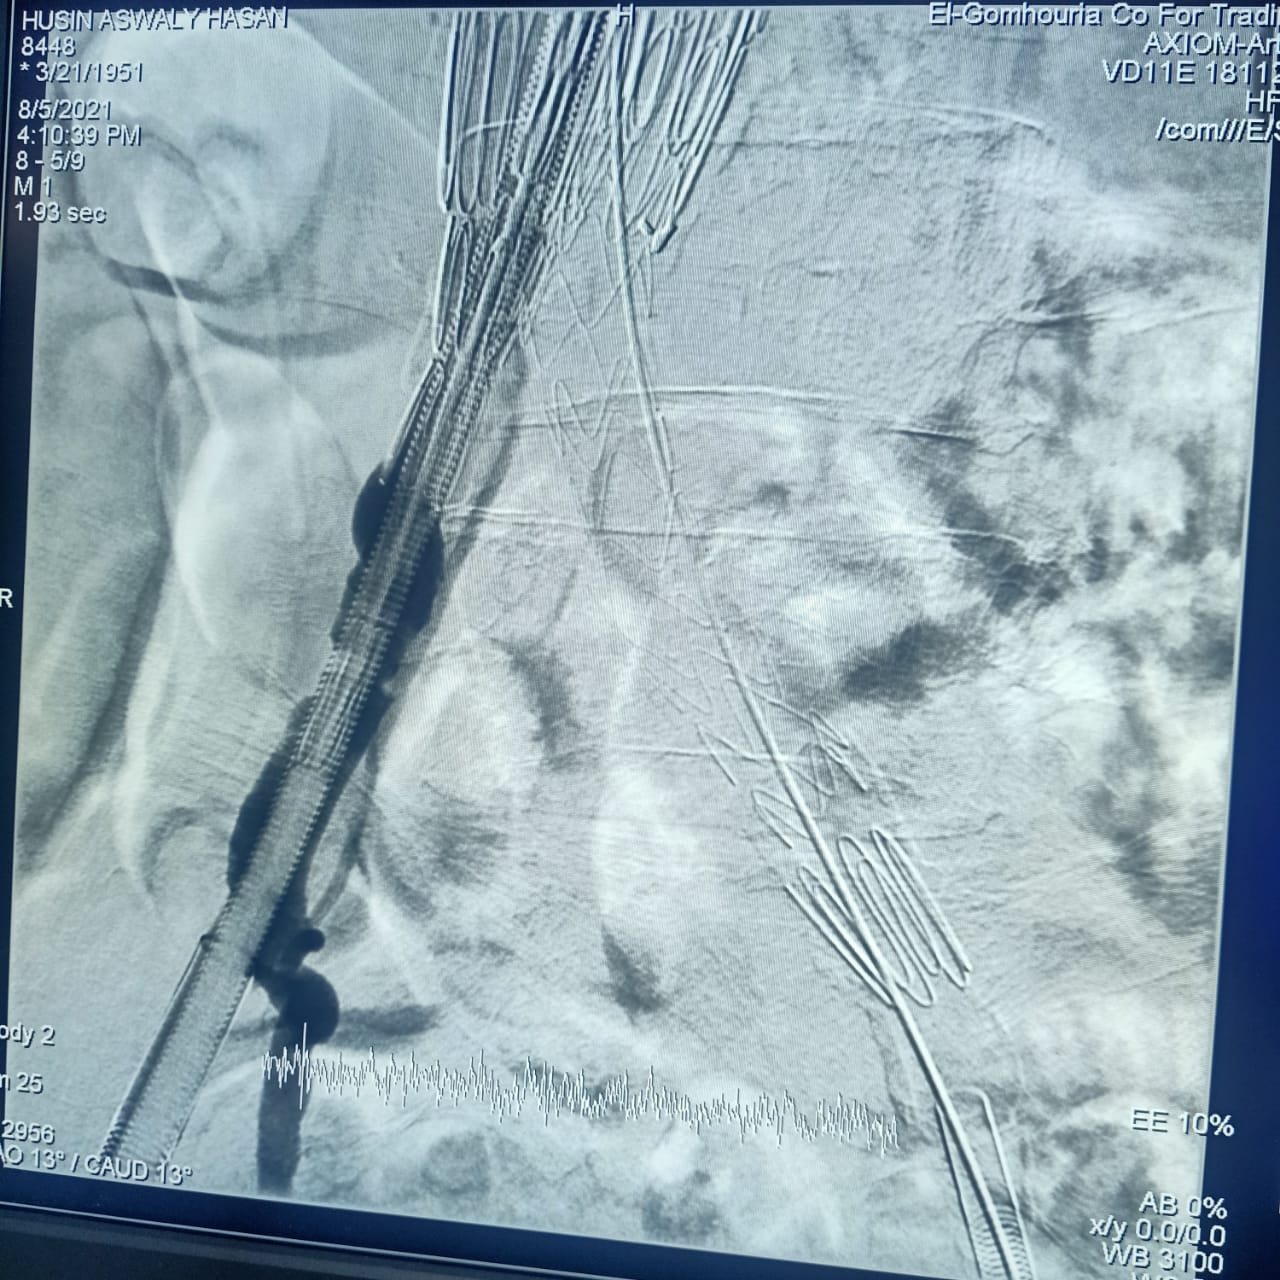

وأشارت هيئة الرعاية الصحية، أن CERAB، EVAR هي من أحدث التقنيات العلاجية لأمراض تمدد وانسداد الشريان الأورطي البطني والحرقفي (بدون جراحة)، من خلال علاج تمدد الشريان الأورطي البطني عن طريق القسطرة باستخدام تقنية الدعامات المغطاة EVAR، وكذلك علاج انسداد الشريان الأورطي البطني والحرقفي عن طريق القسطرة باستخدام تقنية الدعامات المغطاة ذات المقاومة العالية للانسداد CERAB، وذلك وفقًا لأحدث ممارسات الصحة العالمية.

وتابعت الهيئة: أن العملية الأولى كانت لعلاج مُسِّن يبلغ من العمر 70 عامًا يعاني من تمدد بالشريان الأورطي البطني وتم علاجه باستخدام تقنية الدعامات المغطاة EVAR، بينما كانت العملية الثانية لعلاج مريض يبلغ من العمر 65 عامًا باستخدام تقنية الدعامات المغطاة المقاومة للانسداد CERAB، مشيرة إلى استقرار الحالة الصحية للمريضين وإجراء العمليات بنجاح على يد أمهر الأطقم الطبية والتمريضية في مستشفى طيبة التخصصي بالأقصر.